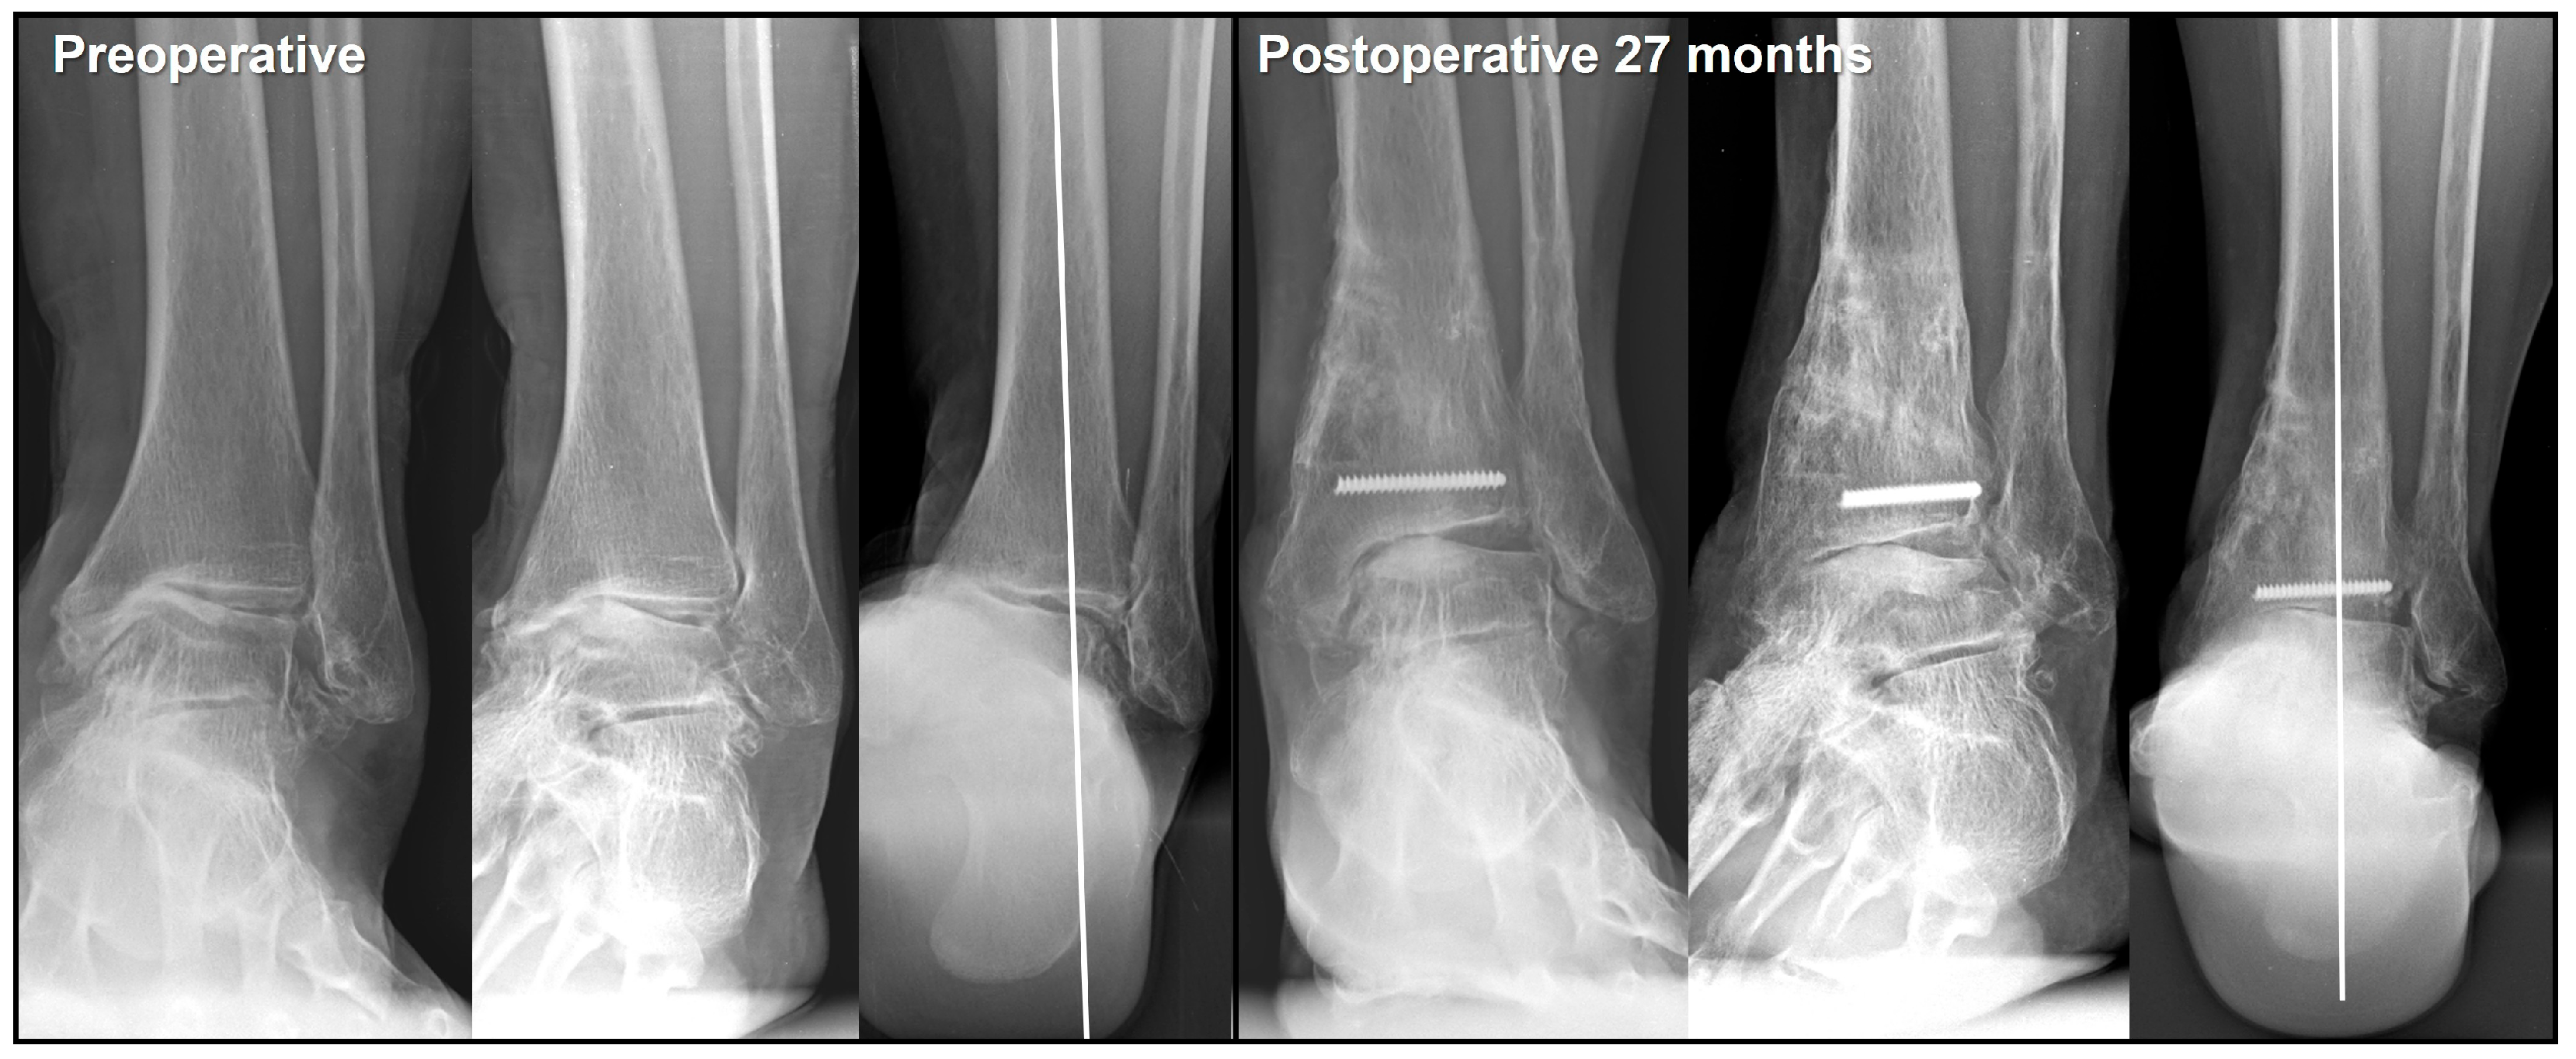

- Choi, J.Y.; Suh, J.S. Joint preserving procedures for Takakura stage IIIB varus ankle osteoarthritis. BMJ Case Rep. 2024, 17, e260585. [Google Scholar] [CrossRef]

- Park, C.H.; Kim, J.B.; Kim, J.; Yi, Y.; Lee, W.C. Joint preservation surgery for varus ankle arthritis with large talar tilt. Foot Ankle Int. 2021, 42, 1554–1564. [Google Scholar] [CrossRef]

- Park, C.H.; Park, J.J.; Woo, I.H. Joint preservation surgery using supramalleolar osteotomy combined with posterior tibial tendon release and lateral ligament augmentation in advanced varus ankle arthritis. J. Clin. Med. 2024, 13, 4803. [Google Scholar] [CrossRef]